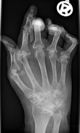

يد عليها أعراض مرض الروماتويد

أشعة اكس على يد مصابة بالروماتويد

التهاب المفاصل الرثياني أو الروماتويد Rheumatoid arthritis (RA) ، هو أحد الالتهابات المزمنة التي تنشأ من خلل في الجهاز المناعي للجسم، وتصيب الأغشية المبطنة للمفاصل ، خاصة المفاصل الصغيرة مثل مفاصل اليدين و الرسغين ، وفي الحالات المتأخرة قد يزيد الوضع ويتفاقم ليحدث تلفاً تدريجياً للمفاصل واعوجاجاً وتشوهاً في بعضها. هذا المرض يصيب الإناث أكثر من الذكور والسبب الأساسي غير معروف ولكن هناك دراسات تشير إلى عمل جهاز المناعة ضد أنسجة الجسم من ضمنها المفاصل.

ويتميز مرض الروماتويد بأنه يبدأ تدريجياً بتيبس والتهاب مفاصل اليدين والساقين في الصباح الباكر، ثم يلاحظ انحراف في مسار اليد عكس الجسم مع خلع في مفاصل اليد، ووجود بثور على سطح الجلد للساقين بنسبة 20%، مع الآم متواصلة، خاصة أثناء النوم وفقدان حركة المفصل، وأخيراً إصابة المفاصل في أنحاء متفرقة من الجسم بتشوهات مثل مفاصل اليدين والركبتين والكاحلين والرقبة والحوض.

ويتم التأكد من التشخيص بعمل فحص للدم والذي يشير هنا إلى ارتفاع في نسبة ترسب الدم ESR ووجود عامل الروماتويد RF وكذلك وجود سي ـ ر ـ بروتين CRP وكذلك عمل أشعة سينية وهي توضح هنا تغيرات في المفاصل مثل تآكل المفاصل وتشوهها وهشاشة العظام.

أماالعلاج فيبدأ تحفظياً بإعطاء المريض المسكنات ومضادات الالتهابات الخاصة بالروماتيود، إضافة إلى العلاج الطبيعي بصفة مستمرة مع عمل تمارين على أداء الأعمال اليومية، ولبس ساندات خاصة بالروماتويد للمساعدة على منع ازدياد التشوهات وعلى أداء عمل المفاصل.

ويجب التعامل مع هذا المرض مبكراً منذ بداية اكتشافه وبأكثر من دواء في نفس الوقت مثل أقراص الميثوتركسات وأدوية الملاريا والكورتيزون الذي يجب أن يستخدم بإشراف الطبيب وبطريقة حذرة ومقننة. وأخيراً العلاج الجراحي للحالات المستعصية ومنها زراعة المفاصل.